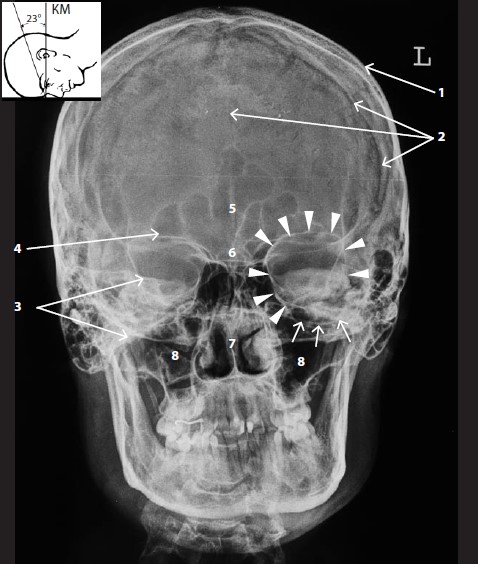

Примеры ортопантомограмм и их анатомия

Раздел: Фотоэссе